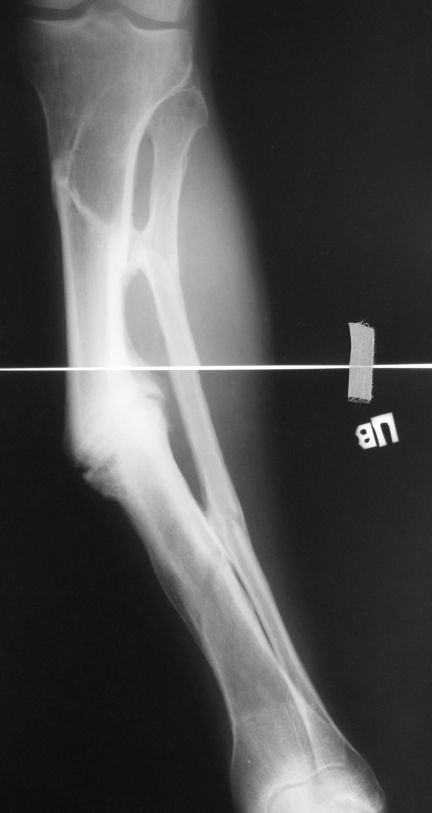

Уважаемые коллеги. Имеется вот такой псевдоартроз. Планируем БИОС tibia стержнем Chm, остеотомию малоберцовой и большеберцовой через зону псевдоартроза. Вопрос! Коррекцию лучше сделать одномоментно во время операции или дозированно в аппарате недели за 2-3, а потом nailing? И ещё делать нормо или с учетом вальгуса гиперкоррекцию?Заранее спасибо за советы!Митрофанов А.И. г. Курган

Одномоментно такой угол устранить трудно, сильно натянутся ткани по наружной поверхности голени. Может и стопа повиснуть. А что по второй проекции?

Мы бы сделали после остеотомии малоберцовой и аппаратной коррекции. Большеберцовую можно исправить за счет растяжения пседартроза. Можно и сделать поперечную остеотомию чуть дистальнее несращения, в этом случае будет удобный вход в периферический отломок. А зону несращения пройти разверткой просто по прямой. Схема в приложении.

Александр Николаевич, вечер добрый! Извиняюсь за отсутствие второй прекции. там тоже ещё та деформация! Дозировано исправлять - не уверен что идиально получится выставить по оси дистальный отломок, а смещение даже на кортикал, не влияющие на консолидацию в аппарате, при формировании канала и введении стержня в условиях вальгуса и рекурвации, ну не знаю. Второй вариант, о котором и вы говорите, думаю более предпочтителен. А если делать остеотомию дистальнее ложняка, то что помешает одномоментно откоррегировать? Парез и при аппаратной коррекции с той же долей вероятности может быть.